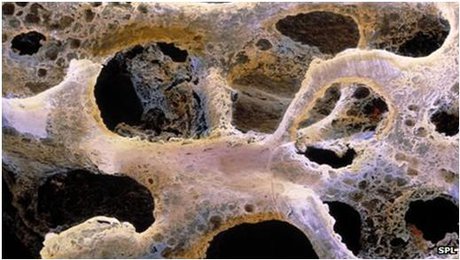

عکس سرطان استخوان. برخی از انواع اصلی سرطان استخوان عبارتند از. سرطان مغز استخوان یکی از انواع سرطان است که به دلیل اختلال در تولید گلبول ها و پلاکت های بدن به وجود می آید. رشد ناهنجار استخوان می تواند بدخیم یا خوش خیم باشد. این تصویر سرطان استخوان است که کاملا روی جمجمه قابل دیدن می باشد.

روش های عکس برداری می توانند به تعیین محل و اندازه ی تومورهای استخوان و گسترش یا عدم گسترش آن ها به سایر نقاط بدن کمک کنند. در این مقاله با علائم سرطان مغز استخوان و نیز روش های درمان آن آشنا می شوید. یک تومور رشد غیر طبیعی بافت در بدن است. سلول های توموری توانایی تنظیم کردن ندارند بنابراین سلول های بیشتری تولید می کنند و منجر به تشکیل یک توده می شوند در حالی که بسیاری از تومورها سرطانی.